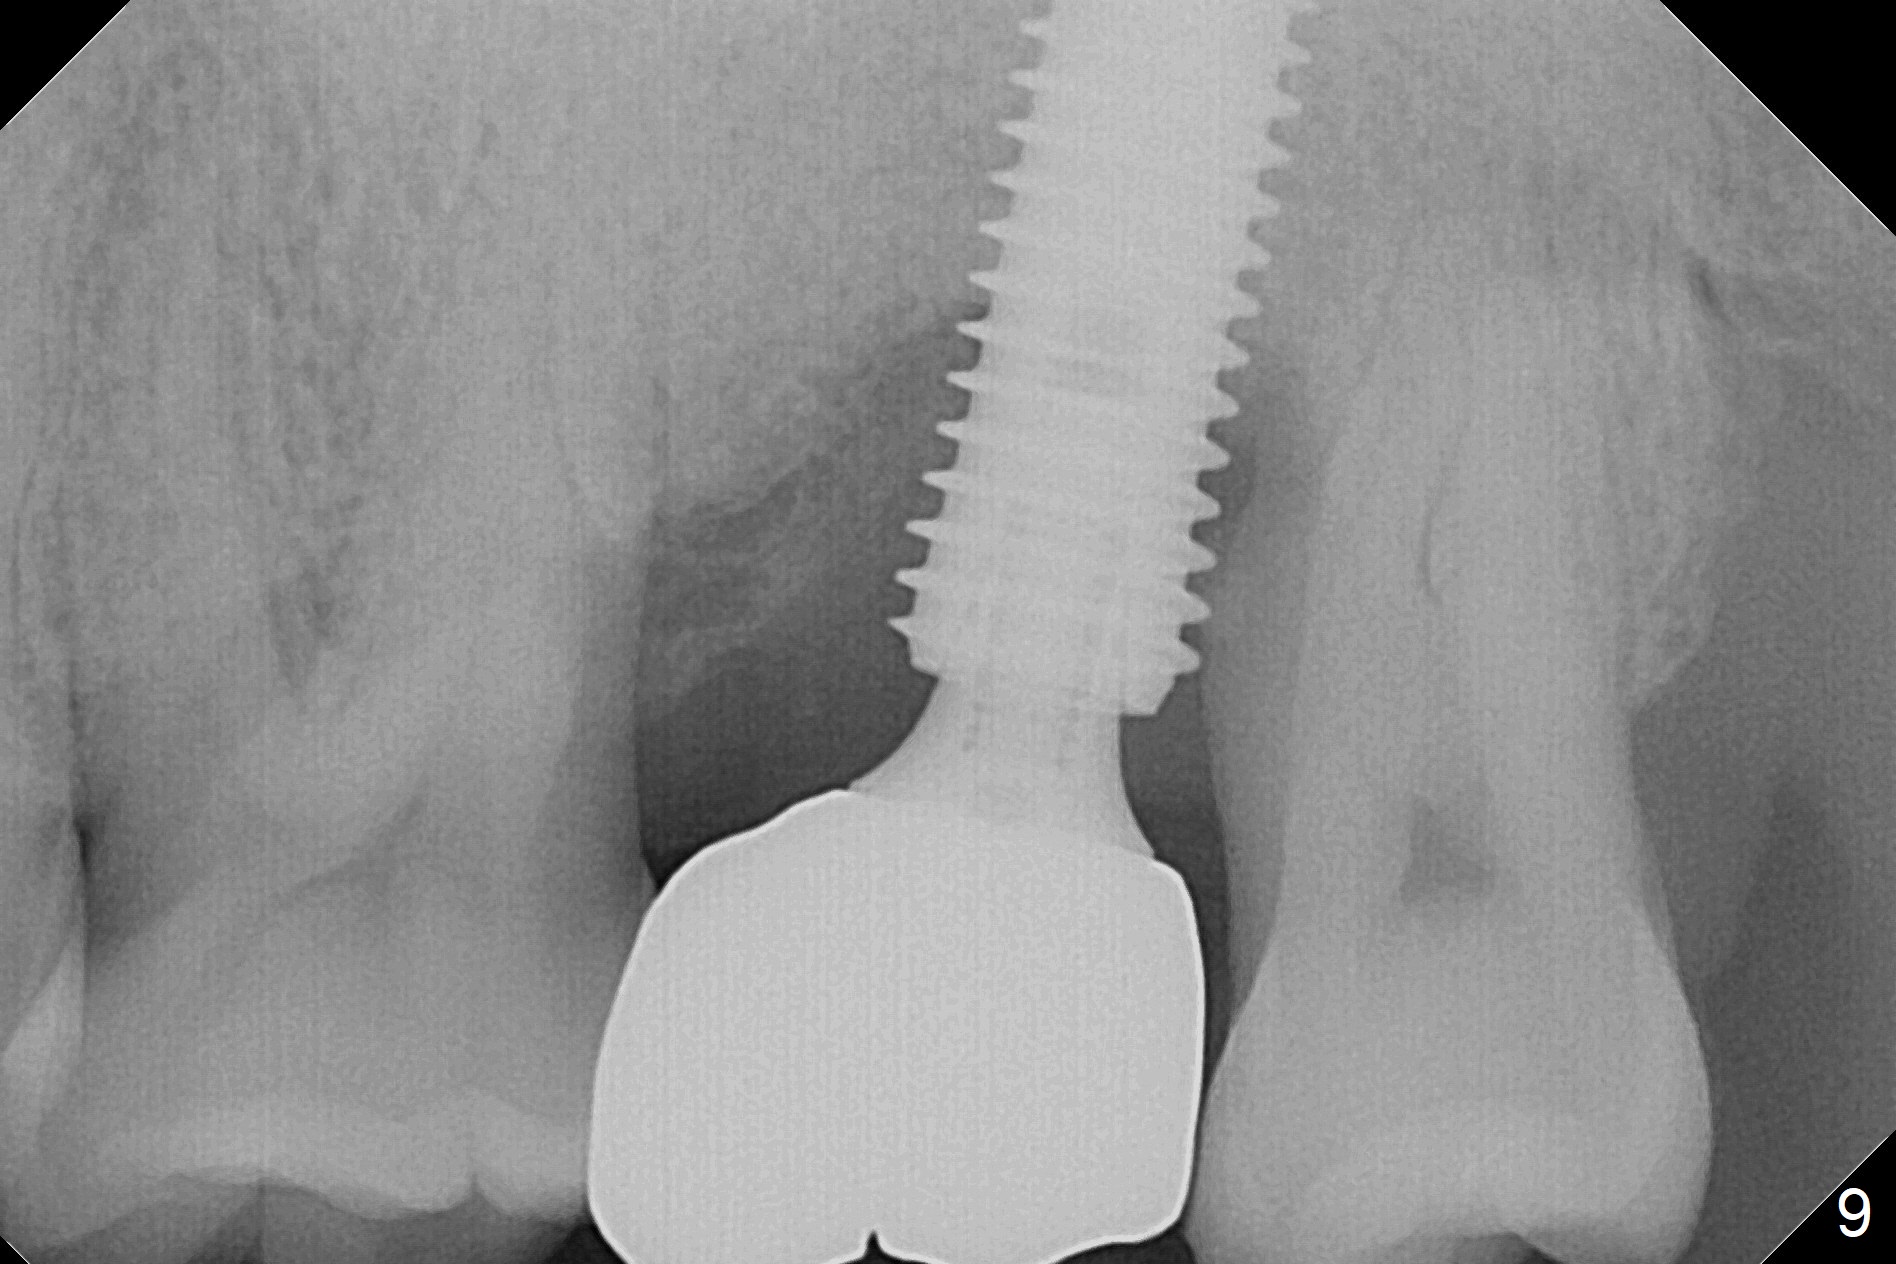

When the tooth #15 is extracted, the buccal plate is found to have been lost. The depth of osteotomy in the native bone is 8.5 mm (Fig.1,2). When a 5.5x15 mm implant is placed (Fig.3), the insertion torque is > 55 Ncm. The implant is palatally placed with a 10x10 mm Osteogen plug being placed in the deep portion of the buccal gap for buccal plate repair (Fig.4 *). The superficial portion of the remaining socket is filled with .5-1.5 mm allograft/autogenous bone/Osteogen (Fig.5 *). The drawback of this procedure is that the abutment is placed prior to placement of the graft. The latter fails to reach the deepest area of the defect. If periimplantitis develops because of insufficient graft, do it again in due time.

There is severe gingival recession: 15 DB, implant plateau exposure, surrounded by healthy granulation tissue, 3.5 months postop. PA shows #15 + implant osteointegration and bone loss coronally (Fig.7). Afterward, the abutment is changed from 6.5x4(4) to 5.5x5(2) mm with fabrication of a provisional. The patient feels that it is easier to brush with a temporary crown. Model shows gingival recession (Fig.8 G) with implant thread exposure distobuccally (I). Although there is no obvious change in bone regeneration 7.5 months postop (2.5 months post cementation, Fig.9) as compared to Fig.7, there is no more distobuccal gingival recession (data not shown; due to use of Water Pik). To avoid the gingival recession, the implant should have been placed more mesial and deeper (Fig.10 green) with use of a longer-cuff (pink) abutment.